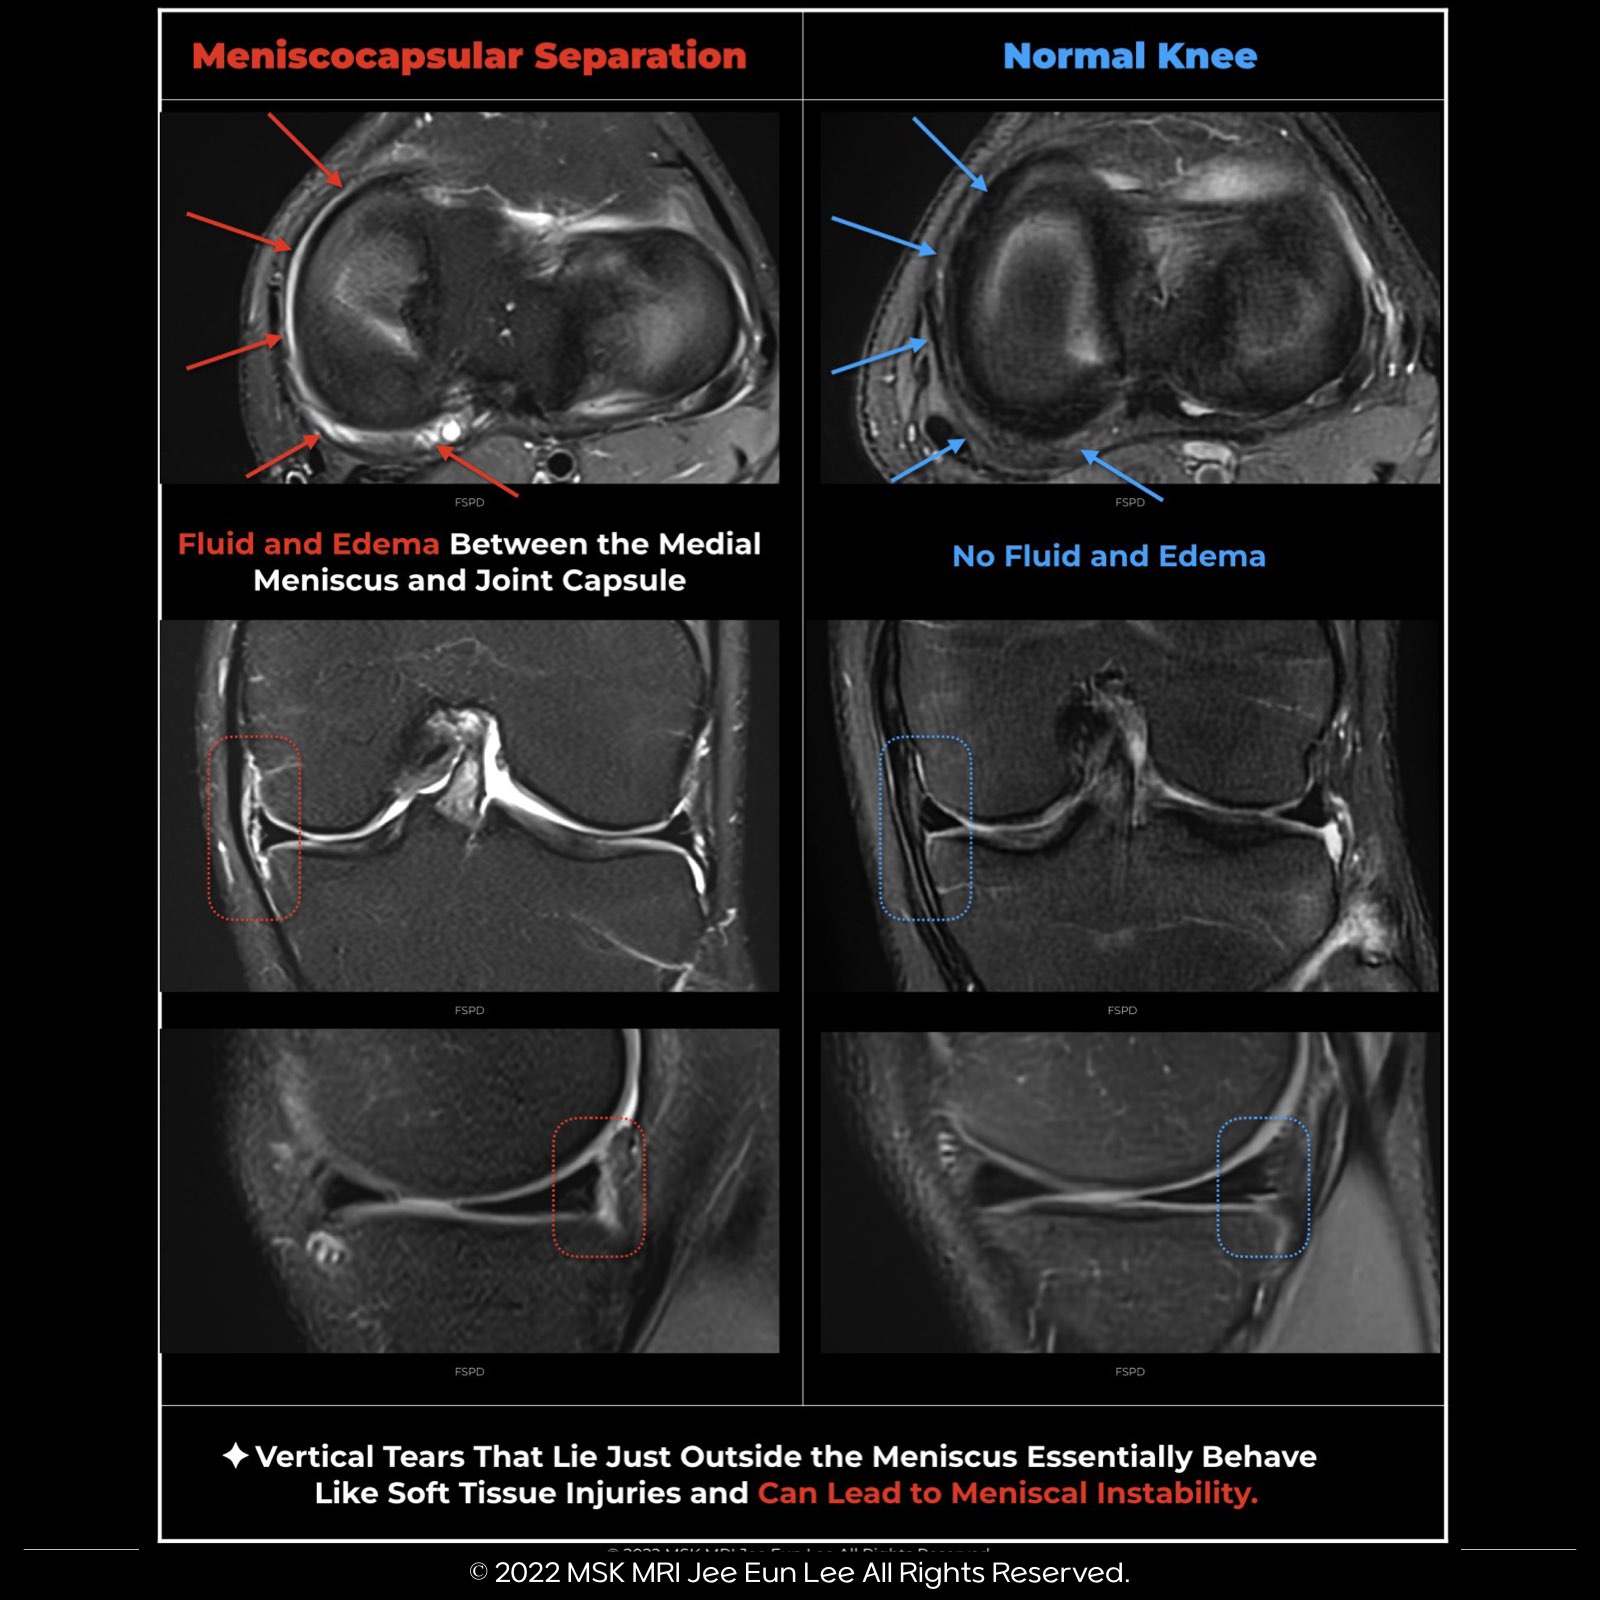

🔵🇰🇷Meniscocapsular Separations

- Vertical tears located just peripheral to the meniscus act similarly to soft tissue injuries, potentially causing instability in the meniscus.

- These kinds of injuries are known as meniscocapsular separations, which occur when the meniscus detaches from the capsule.

🔵🇰🇷Indicators of a medial meniscocapsular separation include:

- The meniscus is displaced in relation to the tibia.

- Presence of fluid in the space between the meniscus and the capsule.

- A tear is located in the outer area of the meniscus.

- An uneven edge of the meniscus.

- Additionally, a tear often occurs in the meniscotibial (coronary) or meniscofemoral ligaments, usually at their point of attachment to the meniscus.